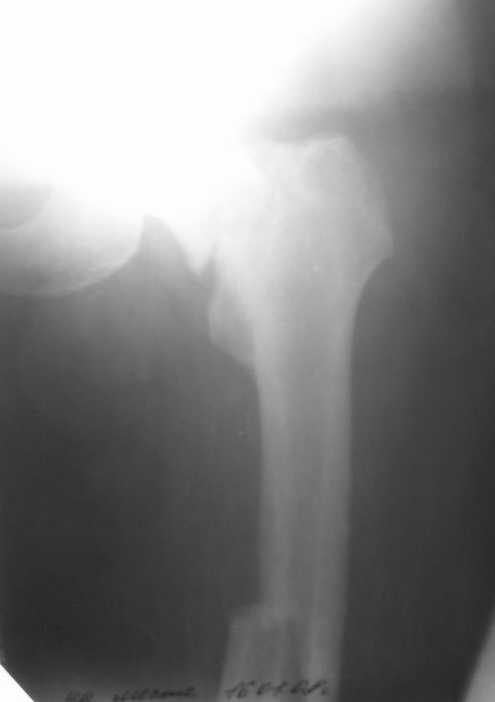

Уважаемые коллеги! Поступил пациент 46 лет после автоаварии от 3.01.

Лечился в ЦРБ. К нам поступил вчера. Имеется оскольчатый перелом диафиза

левого бедра, перелом медиального мыщелка, краевой перелом надколенника.

У нас, кроме того, выявили перелом шейки бедра. Перелом закрытый,

Планируем закрыто фиксировать мыщелок и надколенник винтами, затем

закрыто заштифтовать бедро. Вопрос возник по перелому шейки: что

предпочесть - длинный PFN или DFN + DHS на шейку?